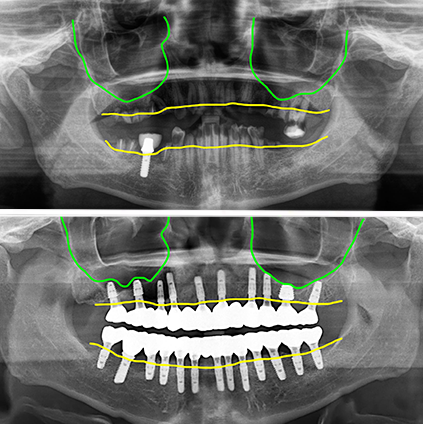

리프팅한 뼈이식 조직도 잘 정착이 되었고 모든 임플란트가 문제없이 골융합이 이루어졌습니다.

잇몸이 좋지 않은 경우가 아닌 충치로 치아를 뽑게 된 경우라 잇몸뼈의 라인이 아주 좋습니다. 이렇게 잇몸뼈의 라인이 평평하면 관리에도 유리하고 심미적으로도 보기에 좋습니다.

4회 내원 치료기간 6개월 전체임플란트 치료완료

전체 내원 4회 (수술, 실밥, 스캔, 세팅) 치료기간 6개월에 모든 치료를 완료하셨습니다. 상악 좌우 구치부에 뼈이식한 부분은 초기고정이 약해서 수술시에 잇몸 속에 임플란트를 넣어두었어요.

그리고 최종 보철을 할 때 절개를 해서 스캔바디를 끼운 후 촬영을 하고 2주 뒤에 최종보철을 세팅했습니다. 일반적으로 일반적으로 초기고정이 좋지 않은 경우는 조금 더 기간을 두고 2차를 진행하는 것이 안전합니다.

이 분은 치료하신 지 3년이 지났고 미국에 계시기 때문에 미국에서 기본적인 점검 하시고 올해 한 번 내원하셨는데 상태가 아주 양호했습니다.